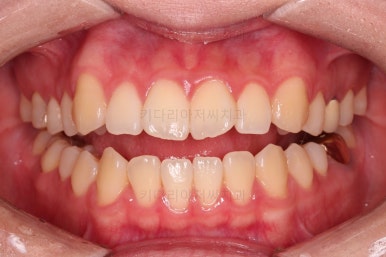

6. 전후 사진 비교

교합, 가지런함, 앞니 각도 모두 좋아졌습니다.

얼굴 모습에서의 변화도 웃을 때 앞니의 느낌, 웃을 때 보이는 앞니의 각도, 아랫입술의 변화 등 모든 면에서 다 좋아진 치료였습니다.

이상 미세 돌출/주걱턱 그로 인한 뻐드러진 치아를 비수술, 비발치로 개선한 치료사례였습니다.